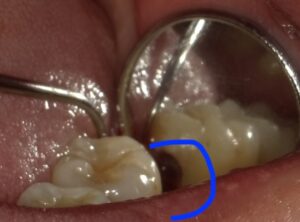

歯茎を開くと青い部分が黒く虫歯になっています。

削って白いセメントを詰めました。